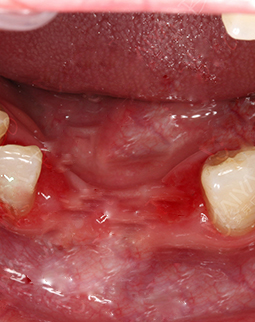

左边是我种牙之前,缺牙很久了,所以这个牙床口长好了。右边是我的种植牙创口,大小和牙根差不多,这个很容易理解,因为种植体就是人造牙根,得有个洞才能把它埋进去,我种牙的创口很小了,基本是微创的,比起过去的切开牙龈种牙好太多了!所以大家不用太担心,你选个好的医院和医生,种植牙还是很靠谱的。